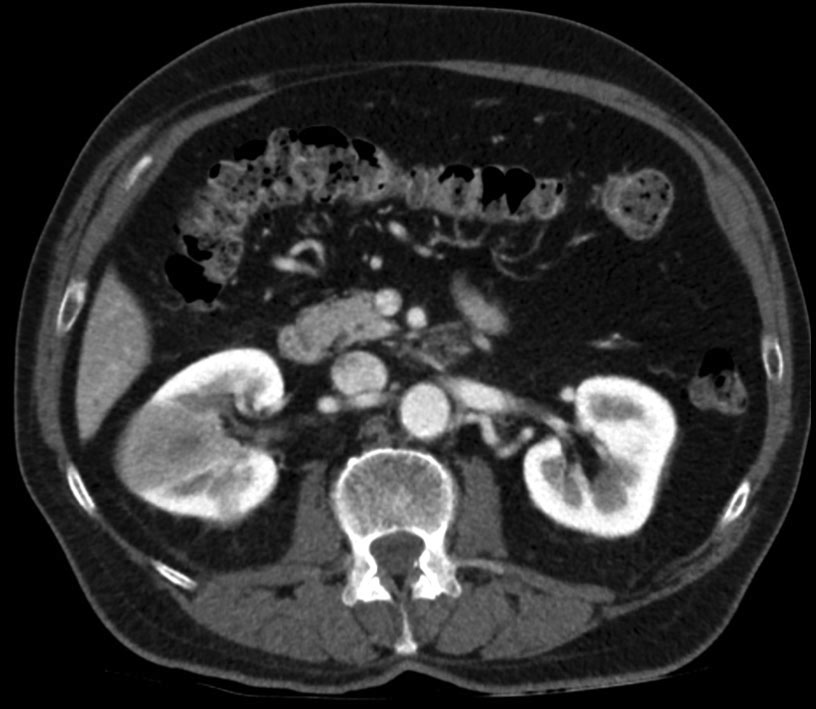

Eco y TC abdominal de control.